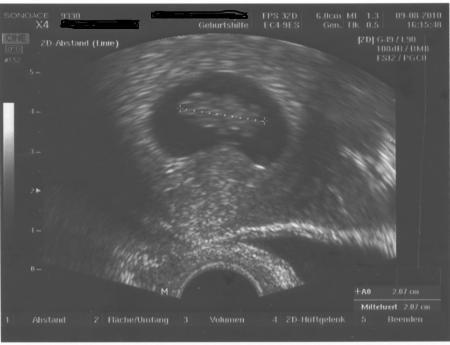

Danke das ihr mich so lieb aufnehmt. Ich im Moment nur ein US Bild bei 8+4 auf dem Rechner. Ich versuchs mal ob ich es schaffen hochzuladen

Hallo, bis jetzt hab ich hier immer nur still mitgelesen aber jetzt wollte ich mich mal vorstellen und würde mich freu wenn ich mich in eure Runde aufnehmt. Ich heiße Christiane bin 30 Jahre alt und wir sind mit Hilfe der KiWu schwanger geworden. Heute bin ich bei 10+5 und gestern hatte wir einen FA Termin. Unser Bärchen ist jetzt 3,7 cm und hat gezappelt. LG